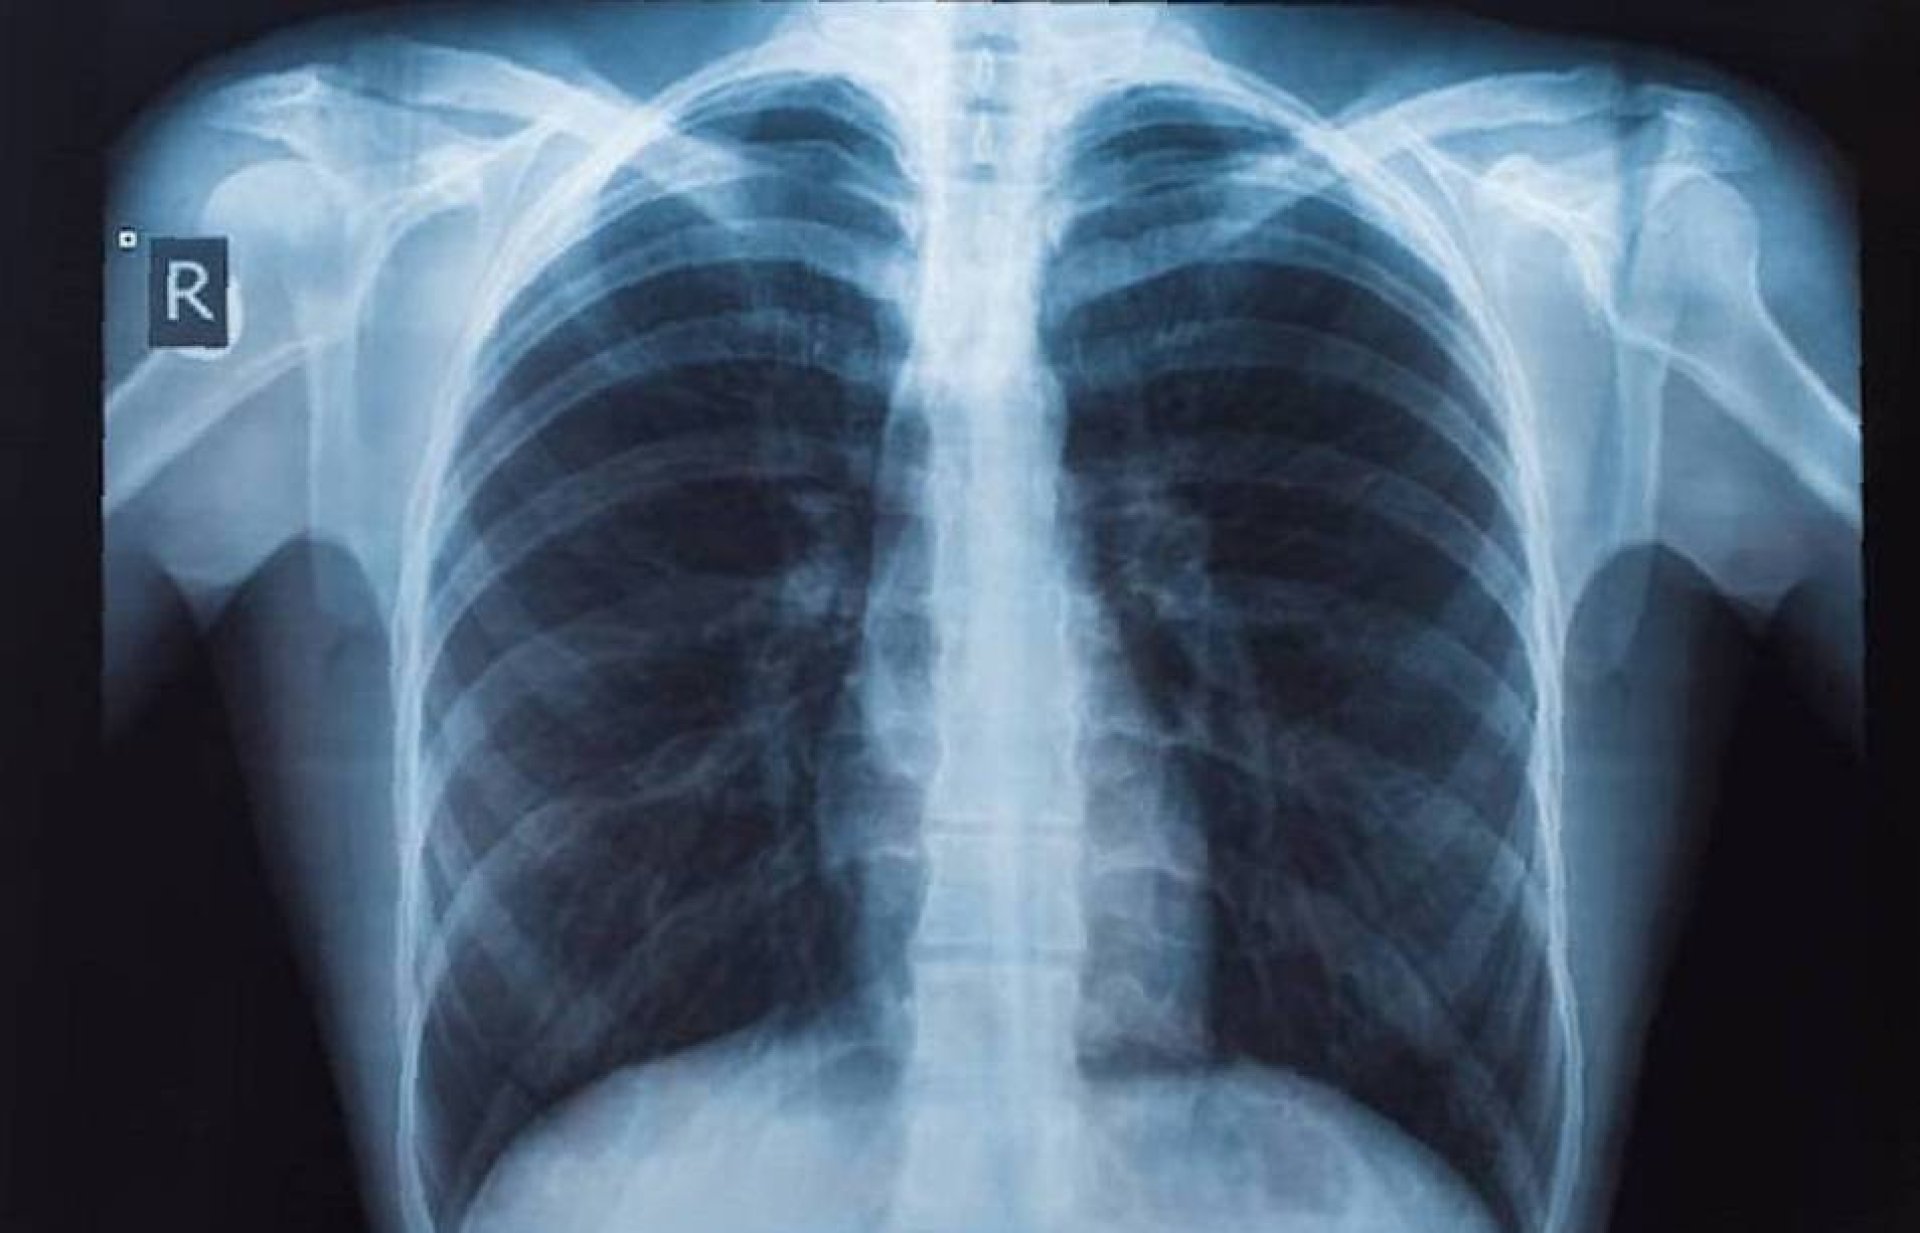

รศ.นพ.ศิระ เลาหทัย ศัลยแพทย์ทรวงอกจากศูนย์ผ่าตัดส่องกล้อง โรงพยาบาลวชิรพยาบาล เปิดเผยว่า มีคำถามยอดฮิตที่ว่า เจอจุดที่ปอด (lung nodule) มีโอกาสเป็นมะเร็งกี่เปอร์เซ็นต์? นั้นหลายครั้งที่เราไปตรวจสุขภาพแล้วพบเจอฝ้าขาว เมื่ออ่านผลรังสีวินิจฉัยพบเจอความผิดปกติในฟิล์มเอกซเรย์ปอด ทั้ง ๆ ที่เรายังไม่มีอาการผิดปกติใด ๆ เลย สิ่งที่สำคัญที่สุด ก็คืออย่าเพิ่งตกใจเราต้องหาสาเหตุของจุดที่เกิดขึ้นมีจริงหรือไม่

โดยวิธีการที่หาสาเหตุที่ดีที่สุดคือการทำเอกซเรย์คอมพิวเตอร์ (CT scan) แต่ไม่ควรที่จะทำเอกซเรย์ซ้ำ เพราะไม่เกิดประโยชน์ เนื่องจากการทำฟิล์มเปรียบเสมือนการถ่ายภาพ 2 มิติ เห็นแค่ด้านหน้า-หลัง ส่งผลทำให้เกิดผลภาพลวงได้บ่อย เปรียบเทียบกับการทำเอกซเรย์คอมพิวเตอร์เห็นรายละเอียด เป็นลักษณะของก้อนเนื้อว่าสงสัยมะเร็งหรือไม่ รวมทั้งมีจริงหรือไม่ หากการทำเอกซเรย์คอมพิวเตอร์ CT scan ไม่มีจุดหรือไม่พบจุด บางที่สิ่งที่เราเห็นจากฟิล์ม คือเงาที่ซ้อนทับกัน เนื่องจากมุมภาพ กรณีนี้มั่นใจได้ ว่าไม่มีอะไร ใช้ชีวิตปกติ ติดตามตรวจสุขภาพประจำปี ในทางกลับกัน เมื่อใดหากเราได้ทำเอกซเรย์คอมพิวเตอร์แล้วเจอว่ามีจุดที่ปอดที่ปอดจริงๆ โดย สาเหตุอาจเกิดได้จาก 1) มะเร็ง (อาจจะเป็นมะเร็งปอดหรือมะเร็งจากที่อื่นกระจายมา), 2) วัณโรคและ 3) อย่างอื่น ๆ เช่น เนื้องอกธรรมดาของปอด หรือ ในช่องทรวงอก ซึ่งปกติเมื่อทำเอกซเรย์คอมพิวเตอร์ (CT scan) มักจะเจอจุดโอกาสเป็นมะเร็งแค่ 1% แนะนำควรพบแพทย์ที่มีความเชี่ยวชาญ เช่น หมอโรคปอดหรือหมอผ่าตัดปอด เพื่อจะดูความน่าจะเป็น หรือติดตามอย่างไรดี

ปัจจุบันประเทศไทยได้ทำ "การเอกซเรย์ปอด" เป็นเครื่องมือสำคัญในการวินิจฉัยระบบการทำงานอวัยวะภายในที่ผิดปกติ ไม่ว่าจะเป็นการตรวจเช็คตั้งแต่บริเวณอวัยวะส่วนทรวงอกจนไปถึงส่วนของโครงสร้างกระดูกที่ครอบคลุมบริเวณปอดและหัวใจ ซึ่งเป็นอวัยวะสำคัญในการดำเนินชีวิตของมนุษย์ ดังนั้นการตรวจเอกซเรย์ปอด (การตรวจเช็คอวัยวะภายในของบริเวณส่วนทรวงอกที่ประกอบไปด้วยโครงกระดูก ปอดและหัวใจเป็นหลัก และได้มีการพัฒนาให้ภาพฉายรังสีถูกสแกนเป็นระบบดิจิตอล ทำให้ผู้ป่วยได้รับการวินิจฉัยที่แม่นยำมากขึ้น